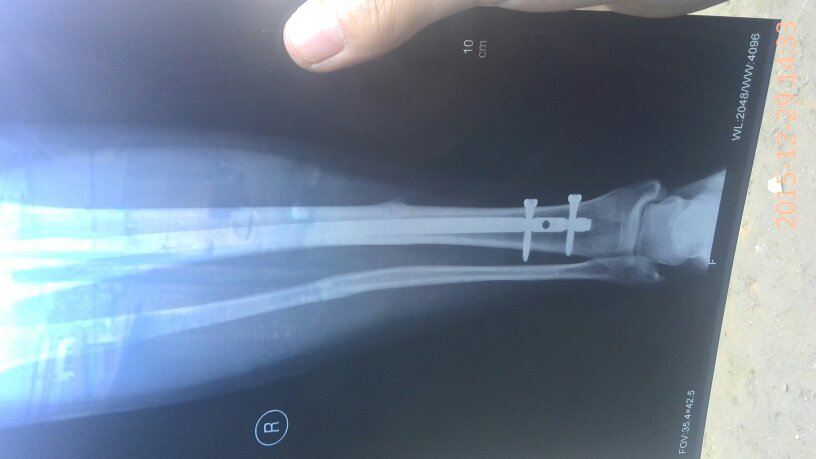

有骨科医生吗?我小腿骨折,上的钢板现在八个月了昨天复查医生说,骨头已经长好,可以取钢板了,我就是问 有骨科医生吗?我小腿骨折,上的钢板现在八个月了昨天复查医生说,骨头已经长好,可以取钢板了,我就是问问八个月了取是不是有点早,心里有点害怕,麻烦帮我看看告诉我,谢谢了…… 点击展开 匿名用户 2015-12-30 19:45 满意回答 怎么骨折的? 匿名用户 2015-12-30 20:55 宝宝知道提示您:回答为网友贡献,仅供参考。 为您推荐: 其他回答 你还是听医生的吧,时间太久了也不太好, 匿名用户 2015-12-30 20:54 没事了,别虚 匿名用户 2015-12-30 20:53 医生的话是对的 华雄40 2015-12-30 19:47 相关问题 小腿骨折钢板固定后,钢板折断且 小腿胫腓骨骨折只放了钢板没有复位这样好吗 我右小腿骨折,手术后有钢板,3个月了外伤口不愈合 是…